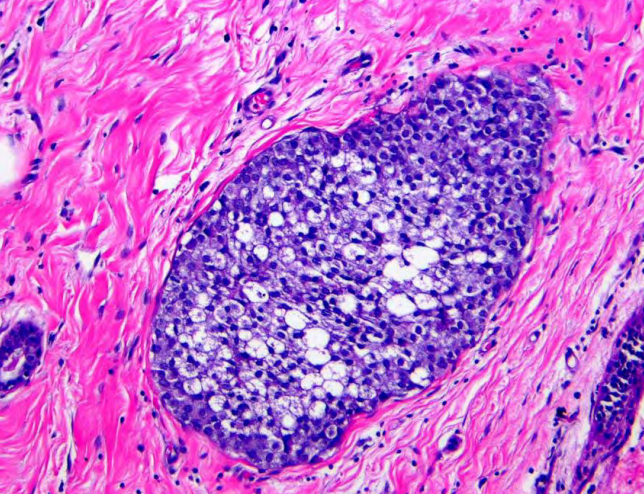

@Janiranavarro

Breast - "occlusive" LVI Lymphatic and/or vascular invasion may be seen in stroma between uninvolved lobules and can sometimes be mistaken for DCIS if the cells completely fill the lymphatic space Dr. Brogi- 2025 Contemporary Issues in Breast Pathology #USCAP #pathology #PathX